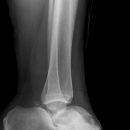

Totale Talusluxation

Talus Fraktur